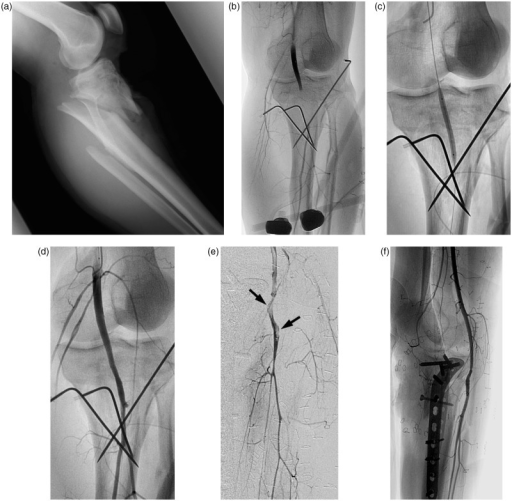

Post-reduction radiographs showing concentrically reduced knee joint. Clinical photograph demonstrates pale, cold foot with absent pulses indicating popliteal artery injury. The combination of knee dislocation and limb ischemia represents a limb-threatening emergency requiring immediate intervention.